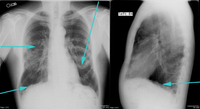

PA and lateral CXR showing calcified pleural plaques

From the collection of Dr Ami Rubinowitz; used with permission